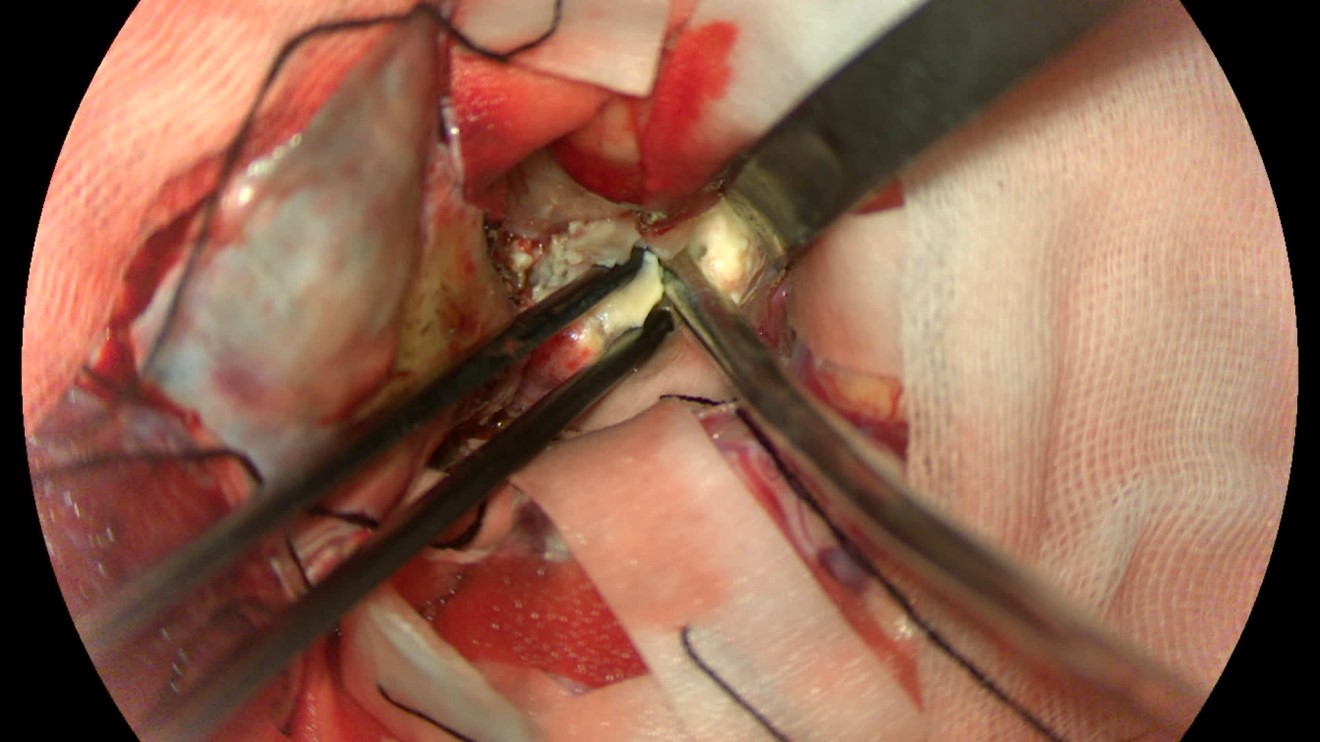

该患者入院后完善常规颅脑影像学检查,左侧颞叶病变,疾病性质不详,转移瘤、胶质瘤、炎症类疾病均不能排除,遂行PET-CT检查,提示左侧颞叶高代谢,淋巴瘤不能排除。组织MDT会诊建议可先行腰椎穿刺查脑脊液脱落细胞学、感染指标,若仍不能确诊,可进一步行开颅病灶切除,术中快速冰冻,根据冰冻结果决定手术手术策略。患者脑脊液脱落细胞学结果:较多淋巴细胞,少许单核细胞及个别中性粒细胞,未见异形细胞,脑脊液常规、生化、脑脊液培养未见细菌生长,诊断仍不能明确,且患者病情进展迅速,患者神志呈昏睡状态,颅脑MRI提示病变较前明显增大(影像学检查间隔两周),且水肿明显加重,遂行开颅病变切除术。术中见部分病变累及蝶骨嵴硬膜,病变质地硬韧,内有多个囊腔,囊内容物为黄色粘稠样脓性物质,留取囊液及实性部分送快速冰冻,在等待冰冻过程中,进一步探查见肿瘤侵犯左侧颞叶,该部位肿瘤质地相对软,无包膜,与周围脑组织无边界,血运不丰富,内有多个囊腔,且肿瘤侵犯侧裂池、颈动脉池,左侧视神经、颈内动脉、大脑中动脉均被病变包绕,且该处肿瘤质地偏硬韧。术中快速冰冻提示组织大片变性坏死,伴胶质增生及淋巴增生。结合病变质地及冰冻结果,考虑为非肿瘤性疾病,可能为炎性病变伴肉芽肿形成可能性大,且肿瘤质地硬韧,累及范围广泛,难以全切,遂行肿瘤大部分切除后结束手术。术后病理结果明确后予以伏立康唑、醋酸卡泊芬净抗真菌治疗。在治疗过程中患者先后出现脑出血、脑梗塞,最终因治疗周期长,花费高、效果不确定等因素,家属放弃治疗,于术后1月去世。